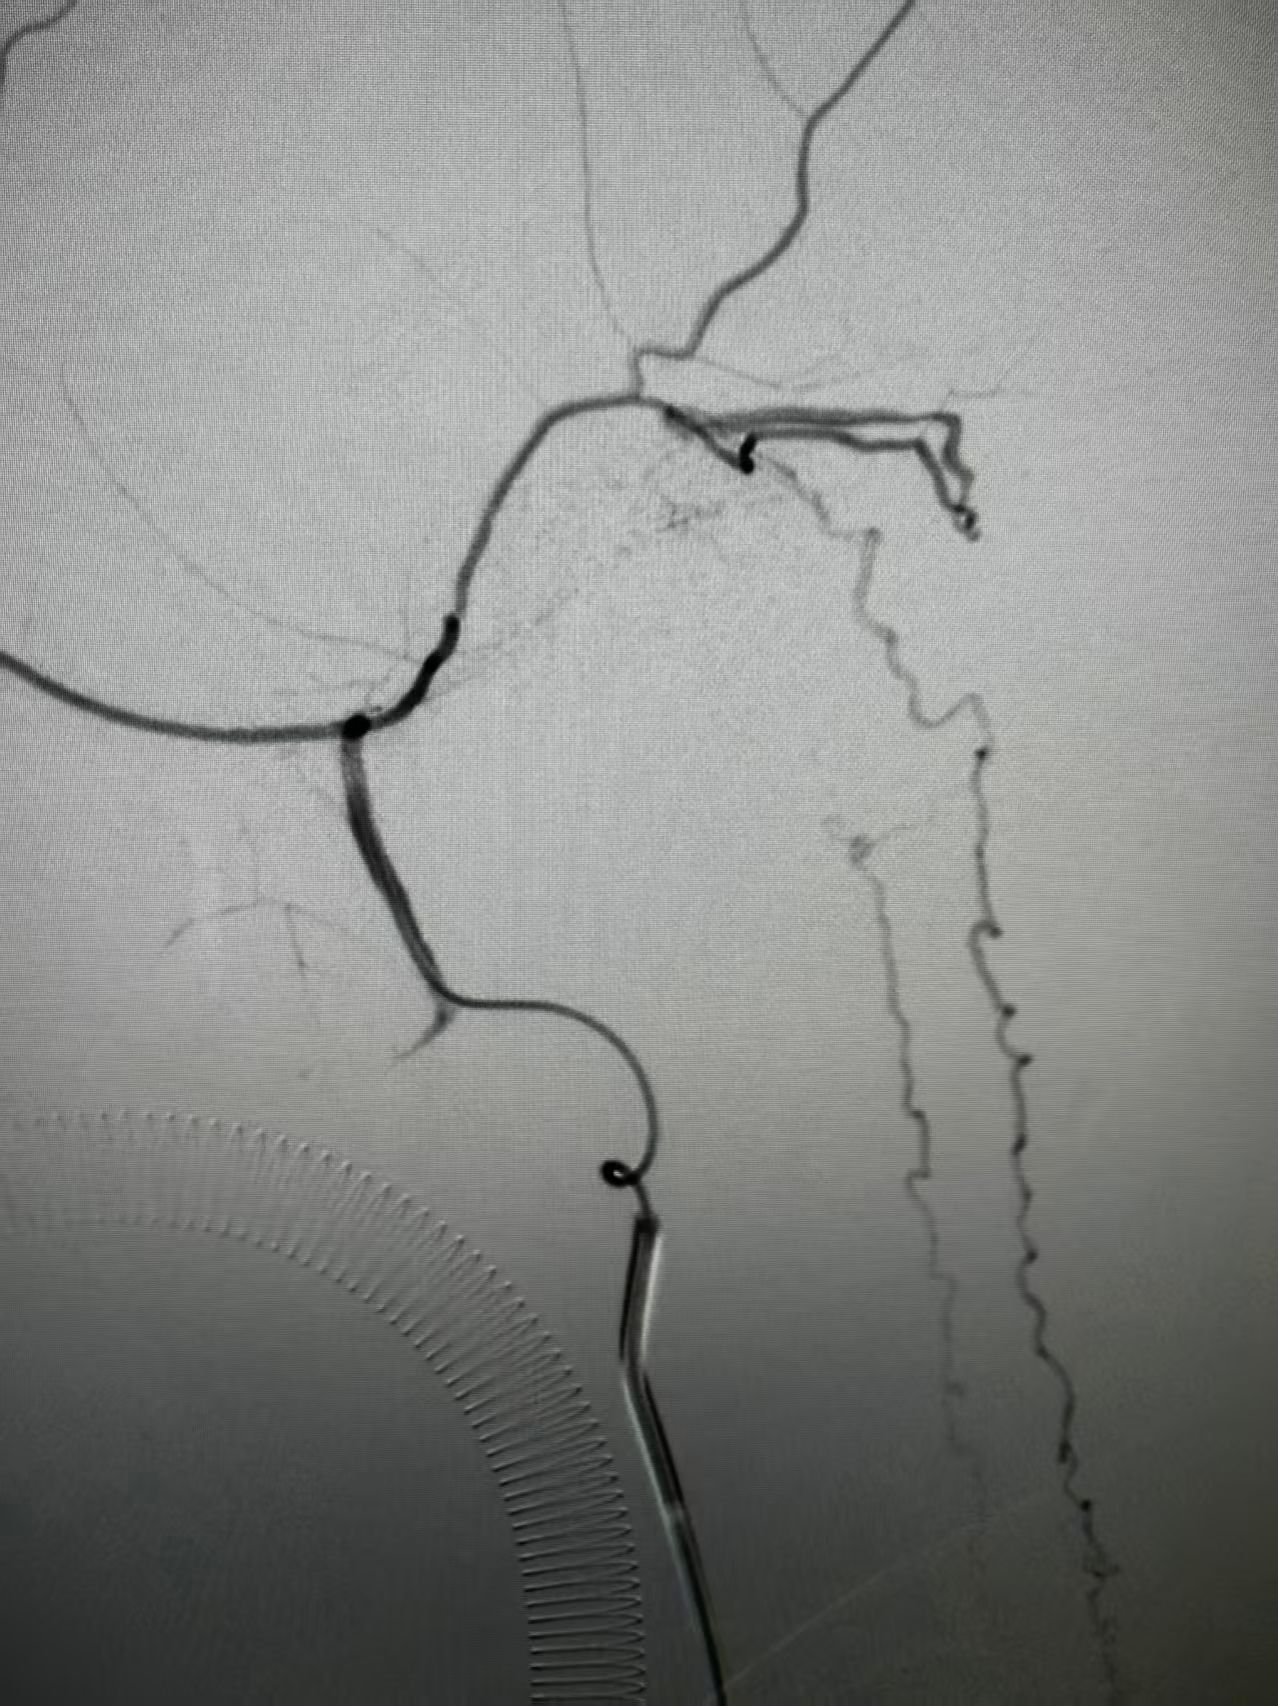

团队结合患者病史、影像学检查以及使用激素后加重的特征,讨论后认为动静脉瘘的可能性较大。但全脊髓造影并未发现硬脊膜动静脉瘘,那么,这个瘘会不会在颅内,只是朝脊髓引流了。根据这个猜测,许刚副主任医师团队为患者进行了全脑血管造影,初步的血管造影并未发现明显病灶。团队并未轻易放弃,又对可疑的各分支血管进行了超选择性造影。最终发现了该患者为脑膜中动脉及枕动脉脑膜支供血的一个非常细小的瘘口。该瘘位于岩骨脊,向下朝脊髓引流,不仔细研究很可能发现不了。

术前脑膜中超选侧位